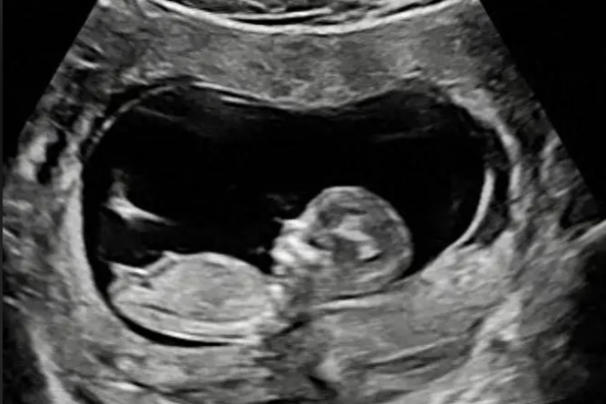

超声检查

B超检查是这个阶段最全面的评估方式:

可以直观看到胎儿心跳搏动

观察胎儿的活动情况,如挥手、踢腿等动作

测量胎儿头臀长,评估生长发育是否符合孕周

检查胎盘位置及羊水量

对于特别焦虑的孕妇,医生可能会建议进行超声检查,这能提供最直观的胎儿存活证据。